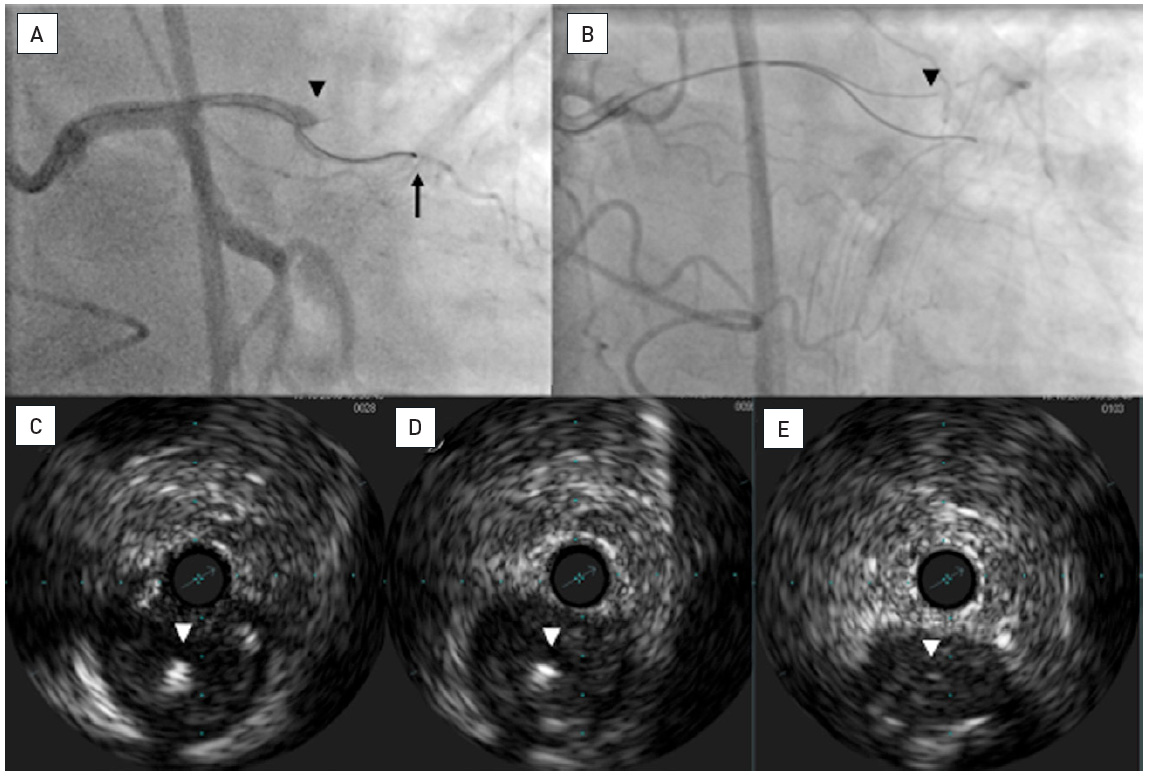

Traveling Wire After Chronic Total Occlusion Percutaneous Coronary

Traveling Wire After Chronic Total Occlusion Percutaneous Coronary Blood Pressure Chronic Total Occlusion chronic total occlusion (cto) of a coronary artery is typically defined as a completely occluded artery without any. Cto is a common condition. Coronary arteries with severe blockages, up to 99%, can often be treated with traditional stenting procedure. chronic coronary occlusion or chronic total occlusion (cto) refers to complete luminal diameter stenosis with resultant. what is. Blood Pressure Chronic Total Occlusion.